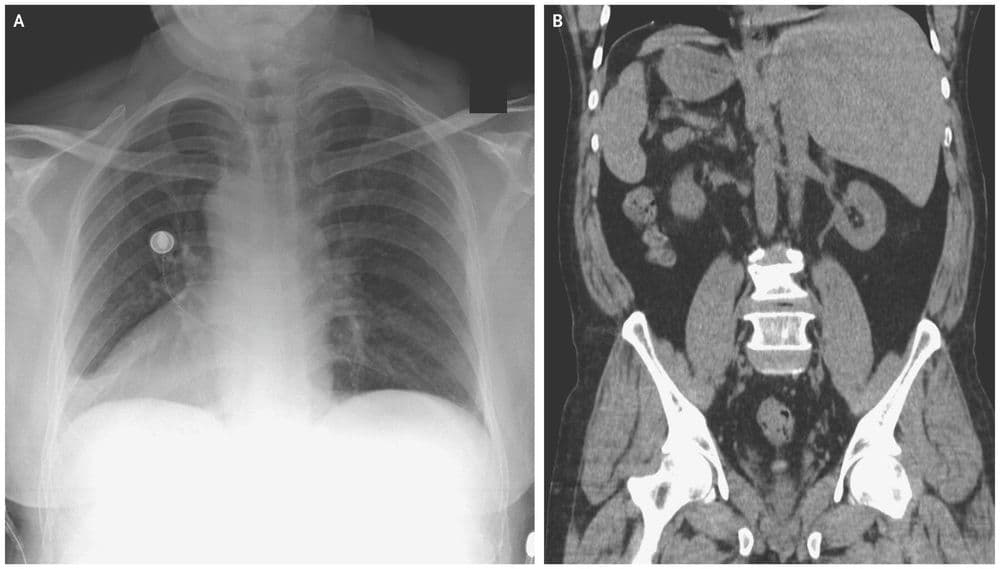

जमालुद्दीन नावाचा हा माणूस नुकतंच पोटदुखीमुळे डॉक्टरांकडे आला होता. डॉक्टरांनी एक्स-रे काढल्यावर त्यांना धक्काच बसला. जमालुद्दीनच्या शरीरातील अवयव विरुद्ध बाजूला होते. त्याचं हृदय उजवीकडे आहे तर यकृत आणि पित्ताशय डाव्या बाजूला आहेत.

त्याच्या पोटात दुखण्याचं कारण होतं पित्ताशयात असलेले खडे, पण पित्ताशय डाव्या बाजूला असल्याने ऑपरेशन करणं अवघड झालं आहे. यासाठी आता नवीन तंत्रज्ञान वापरून त्याच्यावर उपचार केले जातील.

मंडळी, या प्रकाराला शास्त्रीय भाषेत Situs inversus म्हणतात. ही एक अवस्था असून यात माणसाच्या शरीरातील प्रमुख अवयव उलट्या दिशेत असतात. एकूण लोकसंख्येच्या अवघ्या ०.०१% एवढ्याच लोकांमध्ये ही अवस्था सापडते. बऱ्याचशा लोकांना आपल्या शरीरात असे उलटे अवयव आहेत हे माहितीच नसतं. त्याचा शरीरावर विपरीत परिणाम देखील होत नसतो.